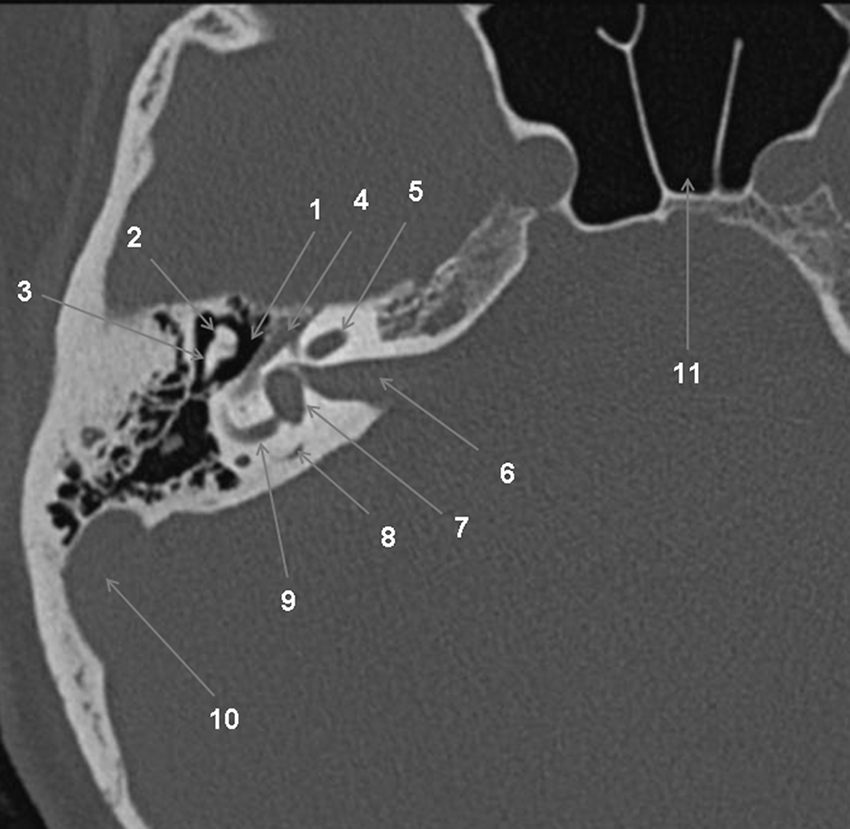

Fig. 62.2 Temporal droit : scanner, coupe transversale.

1. Récessus épitympanique. 2. Tête du malléus. 3. Branche courte de l’incus. 4. Nerf facial, portion tympanique. 5. Cochlée. 6. Méat acoustique interne. 7. Vestibule. 8. Conduit endolymphatique. 9. Conduit semi-circulaire latéral. 10. Sinus sigmoïde. 11. Sinus sphénoïdal.

Source : CERF, CNEBMN, 2022.